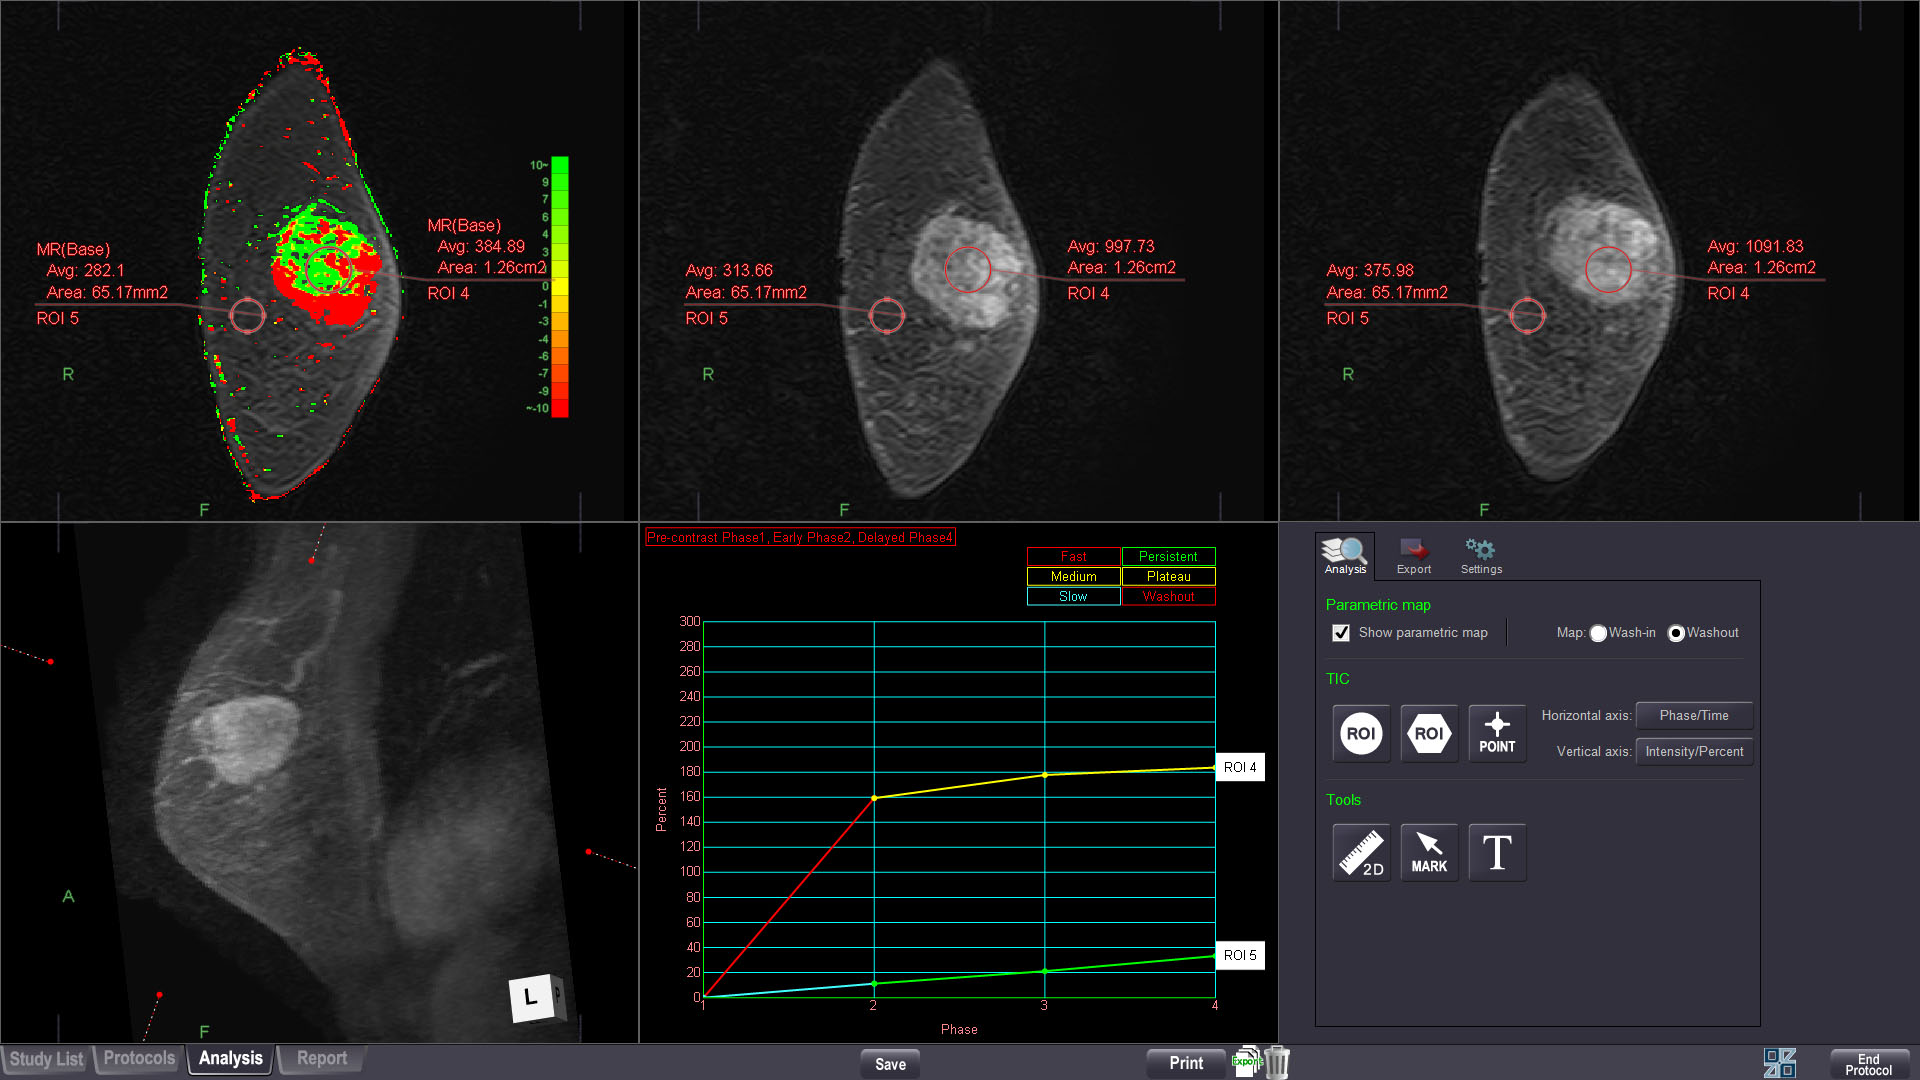

MR MULTIPARAMETRIC ANALYSIS

Using DCE MR images, this protocol displays high precision time-intensity curves for tissue characterization, with BI-RADS and general curve standardizations.